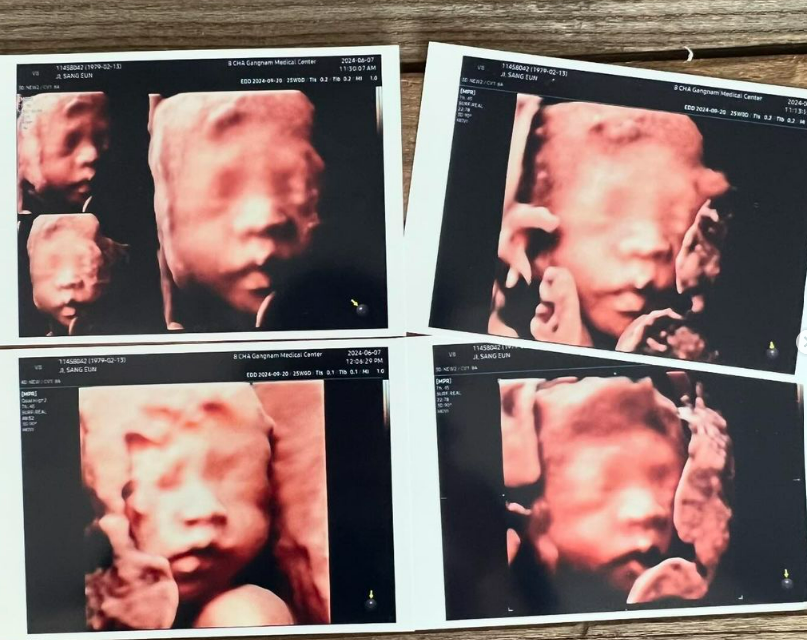

지상은은 최근 방송된 '동상이몽 시즌2'에서 임신 소식을 전하며 많은 관심을 받았어요. 46세라는 나이에 시험관 시술을 9번 시도한 끝에 드디어 임신에 성공했다고 밝혔습니다. 이는 연예계에서도 고령 임신으로 주목받는 이슈입니다.

지상은은 결혼 후 자연 임신이 어려울 수 있다는 의사의 권유로 시험관 시술을 시작했습니다. 처음에는 쉽게 임신된 듯했으나 여러 차례 유산을 겪고, 2년이라는 긴 시간 동안 많은 노력을 기울인 끝에 성공을 이뤄냈습니다.